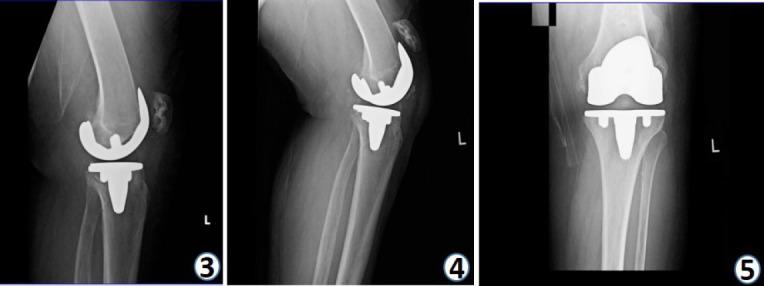

本研究重点介绍了一名75岁女性患者的病例,该患者有双侧膝关节置换病史,因左膝着地摔倒后出现亚急性髌腱断裂。

该患者一年前进行了左全膝关节置换术,前来进行一年的随访。她在受伤3周后就诊,X线显示髌骨高位及小的胫骨结节撕脱骨折,但她左膝疼痛不明显,主动伸直功能也未丧失。尽管患者髌腱损伤严重且呈亚急性表现,但由于其左膝总体功能存在矛盾性保留,建议采取包括物理治疗和职业治疗在内的保守措施而非手术治疗。

展示该患者的病例可能有助于进一步了解髌腱断裂和胫骨撕脱骨折,特别是那些使患者能够保留膝关节力量和伸肌功能从而避免手术的因素。